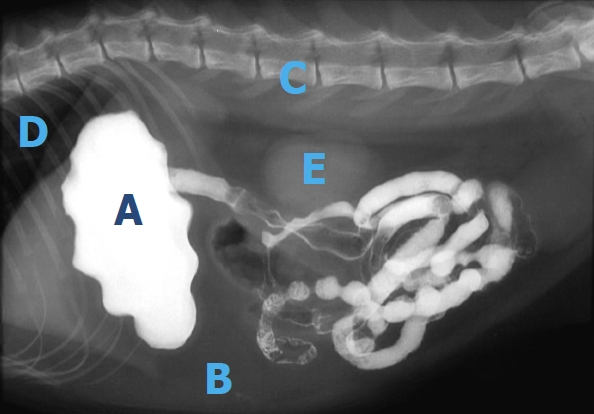

Q

Associez les lettres aux opacités

1. A-métal, B-gras, C-minéral, D-air, E-Tissu mou

2. A-gras, B-Tissu mou, C-minéral, D-air, E métal

3. A-métal, B-Tissu mou, C-minéral, D- air, E gras

4. A-roche, B-papier, C-ciseaux, D-air, E-eau

A

1. A- métallique, B- adipeux, C- minéral, D- air, E- Tissu mou